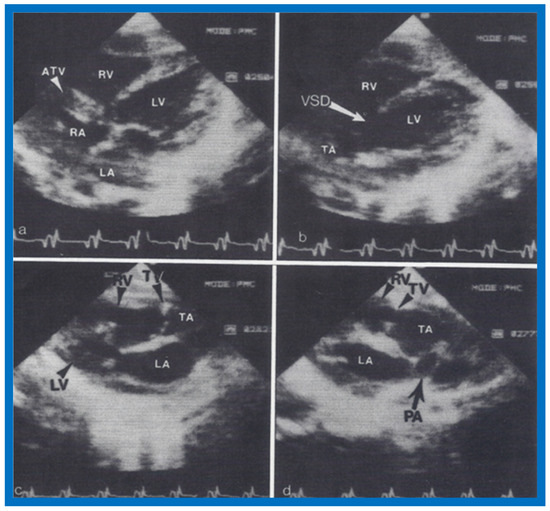

6. Echocardiographic Features of Tricuspid Atresia

The M-mode and two-dimensional echocardiographic features of tricuspid atresia were discussed in the author’s first book on tricuspid atresia, written in collaboration with his colleague, Dr Wesley Covitz at the Medical College of Georgia [7]. The two-dimensional (2D) echocardiographic pictures in 1982 were crude (Figure 14) [7]; however, they represented the state of the art echocardiography machines of that time.

Figure 14.

Selected video frames from apical four-chamber view of a two-dimensional (2-D) echocardiographic study demonstrating dense band of echoes between the right atrium (RA) and hypoplastic right ventricle (RV). Line drawings are shown beneath the 2D frames. Note that the mitral valve is closed in the left image while it is open in the right image. The atretic tricuspid valve echoes remain unchanged. LA, left atrium; LV, left ventricle. Reproduced from Covitz W., Rao P.S. [7].

Figure 15.

Selected video frames from subcostal four-chamber view of a two-dimensional (2-D) echocardiographic study demonstrating atretic tricuspid valve (ATV) (thick arrow), represented by a dense band of echoes between the right atrium (RA) and hypoplastic right ventricle (RV). In (A), the mitral valve (MV) is closed, while in (B), it is open. Note the improvement from the pictures shown in Figure 14. LA, left atrium; LV, left ventricle. Reproduced from Rao P.S. [35].

Figure 16.

Apical four-chamber view pictures of another infant with tricuspid atresia (large arrows in A,B) with ostium primum atrial septal defect (slanted arrow in B). Note small right ventricle (RV) and a ventricular septal defect (small arrows in A and B). LA, left atrium; LV, left ventricle; RA, right atrium. Reproduced from Covitz W., Rao P.S. [36].

More recently, the author reviewed the echo-Doppler evaluation of tricuspid atresia [37,38,39]; these findings will be presented. M-mode echocardiography, while not diagnostic, is useful for evaluating the size of the left atrium (LA) and left ventricle (LV) and LV function. On 2D echocardiography, the atretic tricuspid valve is visualized directly as a dense band of echoes at the site where the tricuspid valve should be in the most frequent muscular type, as shown in Figure 14, Figure 15, Figure 16 and Figure 17. This anatomy is better demonstrated in apical and subcostal four-chamber views than in other views. The other types, namely membranous, valvular, Ebstein’s, atrioventricular septal and unguarded valve with muscular shelf (Figure 18) [40], are rare and may also be recognized on 2D echocardiography.

Figure 17.

Selected video frames from apical four-chamber, 2-dimensional echocardiographic views of a neonate with tricuspid atresia showing an enlarged left ventricle (LV), a small right ventricle (RV) and a dense band of echoes at the site where the tricuspid valve echo should be (ATV) (thick arrow) with closed (A) and open (B) mitral valve. A moderate sized ventricular septal defect (VSD) (thin arrows) is shown. LA, Left atrium; RA, Right atrium. Reproduced from Rao P.S. [39].

Following the demonstration of the atretic tricuspid valve, the sizes of the cardiac chambers were evaluated both by M-mode (Z scores) and 2D echocardiography; enlarged RA, LA and LV, and a small RV, were seen (Figure 14, Figure 15, Figure 16 and Figure 17). Pulsed (not shown) and color Doppler (Figure 19) studies were helpful in illustrating the right-to-left shunt across the patent foramen ovale or atrial septal defect. Contrast study using agitated saline with 2D imaging clearly demonstrated successive opacification of the RA, LA, LV and then the RV in that order, but such a study is not necessary for diagnosis.

The relationship of the great arteries is examined next in order to classify them into various types [41]. The relationship of the great arteries is established by following the vessels arising from the ventricles until pulmonary bifurcation or aortic arch. In Type I patients with normally related great arteries, the aorta arises from the LV (Figure 20), while in Type II patients with transposition of the great arteries, the PA arises from the LV (Figure 21 and Figure 22). In Type III patients, it may be little more difficult to assign the great artery relationship, and sometimes angiography is needed. In type IV with truncus arteriosus, the limited data [22] suggest that this can be done by echocardiography (Figure 23 and Figure 24).

Two-dimensional echocardiographic video frames demonstrating (a) atretic tricuspid valve (ATV) between the right atrium (RA) and right ventricle (RV), (b) a large subtruncal ventricular septal defect (VSD), (c) thickened and somewhat domed truncal valve (TV) leaflets, and (d) origin of the pulmonary artery (PA) from the posterior aspect of the truncus arteriosus (TA). LA, Left atrium; LV, left ventricle. Reproduced from Rao P.S., et al. [22].

Figure 24.

Video frame from a two-dimensional echocardiographic and color Doppler study demonstrating (A) atretic tricuspid valve (ATV) between the right atrium (RA) and right ventricle (RV) and blood flow from the left atrium (LA) into the left ventricle (LV) across the mitral valve. The RV (arrow) is very small and hypoplastic. (B) LV and RV with a large ventricular septal defect (VSD) below the truncus arteriosus (TA). Turbulent flow across the truncal valve suggests truncal valve stenosis. (C) origin of the pulmonary artery (PA) from the TA by color flow (arrow), and (D) division of right (RPA) and left (LPA) pulmonary arteries from the PA (labeled in d) in a short-axis view. TV, truncal valve leaflets. Reproduced from Rao P.S., et al. [22].